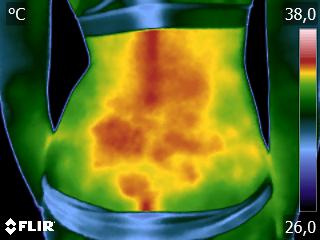

Como no caso do termograma abaixo de uma aplicação de laserterapia em antebraço direito. Esta aplicação foi realizada com a técnica Termoguiada para uma melhor precisão dos pontos de aplicação. Isso porque, como a paciente estava com muita dor e a espessura do feixe do laser é menor que 0,3 cm, deve-se ter muita precisão na aplicação da radiação laser para se promover a analgesia.

Isso potencializa os efeitos da terapêutica, pois a radiação será aplicada exatamente nos pontos de maior necessidade, não desperdiçando luz ao longo da sessão. Assim, a aplicação da laserterapia gera melhores resultados para o seu paciente e para a sua terapêutica.

Porém, somente quem possui o conhecimento da termografia associado ao conhecimento clínico da Técnica Termofuncional consegue fazer uso prático deste método de forma a gerar resultados na sua clínica.